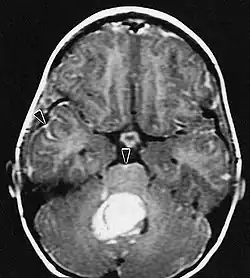

L'IRM montre généralement une lésion de contraste massive impliquant le cervelet. Comme mentionné ci-dessus, le médulloblastome a une forte propension à infiltrer localement les leptoméninges ainsi qu'à se propager à travers l'espace sous-arachnoïdien, impliquant les ventricules, la convexité cérébrale et les surfaces leptoméningées de la colonne vertébrale. Par conséquent, il est nécessaire de mettre en résonance tout l'axe crânio-spinal.

Les patients souffrent d'une variété de symptômes caractéristiques d'une lésion massive focale ou multifocale. L'IRM montre généralement des tumeurs avec un rehaussement de contraste homogène au sein de la substance blanche périventriculaire profonde. La multifocalité et le rehaussement inhomogène sont typiques des patients dont le système immunitaire est affaibli. L'analyse du lymphome du SNC est extrêmement importante dans le diagnostic différentiel de la néoplasie cérébrale. Il est à noter que l'administration de corticoïdes peut entraîner la disparition complète du rehaussement, rendant difficile le diagnostic des lésions. Par conséquent, si un lymphome du SNC doit être pris en compte dans le diagnostic différentiel, les corticoïdes doivent être évités à moins que l'effet de masse ne provoque un problème grave et immédiat chez le patient.